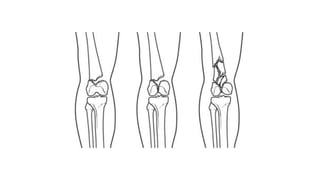

This document discusses femoral fractures, categorized by their location and severity, with classifications such as Garden classification. It outlines the types of fractures, including valgus impacted, non-displaced, partially displaced, and fully displaced, along with their surgical treatment options. Additionally, it briefly describes distal femur fractures, which occur just above the knee joint.